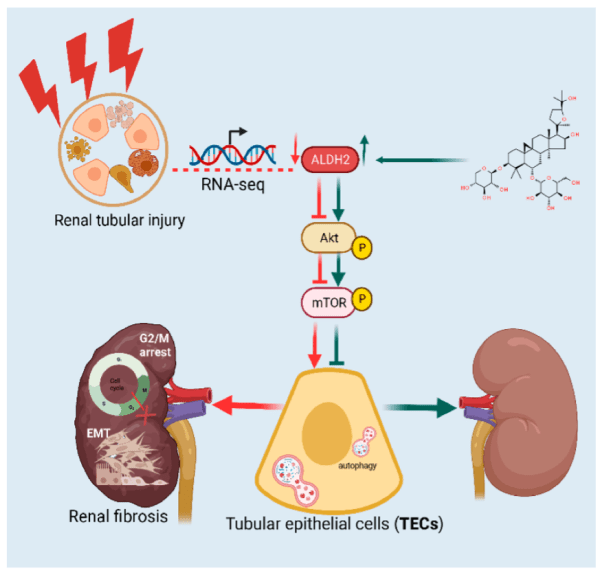

B7-33

B7-33 is a synthetic peptide, a derivative of relaxin, derived from the B-chain of human relaxin-3 (also known as INSL7 or RLN3), comprising amino acids 7-33 and the B-chain. This specific peptide is less well-known; however, it has gained attention in the research world due to its individual actions and therapeutic potential. As previously stated, a major mediator in renal fibrosis is TGF-β, which activates downstream pathways involving Smad2 and Smad3. This leads to increased collagen deposition and fibrotic changes in kidney tissue. Research has found that inhibiting the signalling pathways of TGF-β can protect against renal fibrosis. Research has indicated that B7-33 can reduce collagen thickness and matrix metalloproteinase-2 (MMP-2) activity, which is essential for collagen degradation.

Interleukin-33 (IL-33) in renal fibrosis is also gaining recognition. Increased IL-33 levels have been associated with inflammatory responses leading to ischemia-reperfusion injury (IRI) and then fibrosis. IL-33 and TGF-β are therefore important mediators in renal fibrosis, offering hope for more effective interventions.

For kidney damage related to hypertension, B7-33 may support the body by;

- Preventing vascular sclerosis

- Reducing interstitial fibrosis

- Protecting against epithelial-to-mesenchymal transition

B7-33 shows vasodilatory effects similar to those of full-length relaxin, these include;

- Vasodilation through nitric oxide-dependent mechanisms

- Reduction of vascular stiffness

- Angiogenic properties that may promote tissue repair

Studies show B7-33 may improve vascular function by promoting angiogenesis and reducing endothelial cell apoptosis, supporting the process of vascular repair.